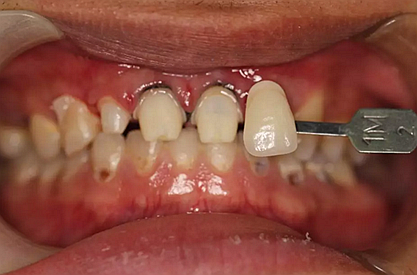

兩周后,主人帶我們往醫(yī)院拆線,取模,比色,為我們重新量身定制了一套堅(jiān)固的“外套”。

第5次復(fù)診的時候,終于讓我們4個兄弟恢復(fù)了正常的容顏。